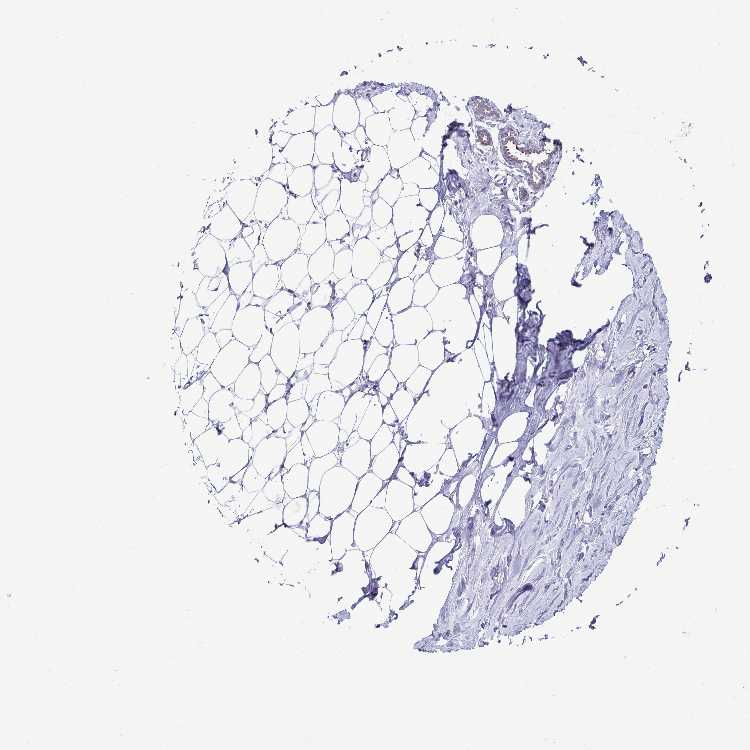

BREAST - Antibody stainingi

Antibody staining in the annotated cell types in the current human tissue is reported as not detected, low, medium, or high, based on conventional immunohistochemistry profiling in selected tissues. This score is based on the combination of the staining intensity and fraction of stained cells.

Each image is clickable and will lead to virtual microscopy that enables deeper exploration of all samples and also displays staining intensity scores, fraction scores and subcellular localization as well as patient and tissue information for each sample.

Antibody HPA063350

Adipocytes Not detected

Glandular cells Not detected

Myoepithelial cells Not detected